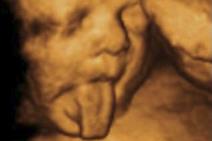

9 najsmešnijih fotografija sa ultrazvučnog pregleda (FOTO)